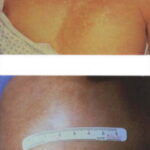

Koebnerization commonly occurs in vitiligo. Lesions frequently develop at sites of trauma, such as mild friction from clothes, or from a cut, burn, or abrasion .

Depending on ethnic color, vitiligo is more or less conspicuous .